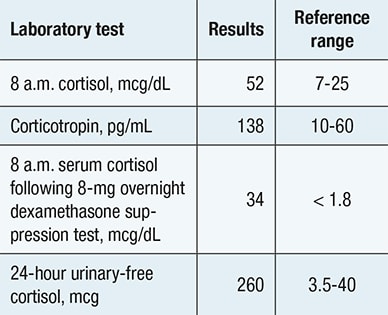

Evaluation confirming adrenocorticotropic hormone-dependent Cushing syndrome

Evaluation confirming adrenocorticotropic hormone-dependent Cushing syndrome

Biochemical evaluation confirming presence of adrenocorticotropic hormone -dependent Cushing syndrome.

Biochemical evaluation confirmed corticotropin (ACTH)-dependent Cushing syndrome. Pituitary-directed MRI demonstrated a normal pituitary gland, and inferior petrosal sinus sampling indicated a nonpituitary source of ACTH secretion. In search of an ectopic neuroendocrine tumor, a chest CT scan identified a 7-by-5-mm nodule in the right lower lobe.